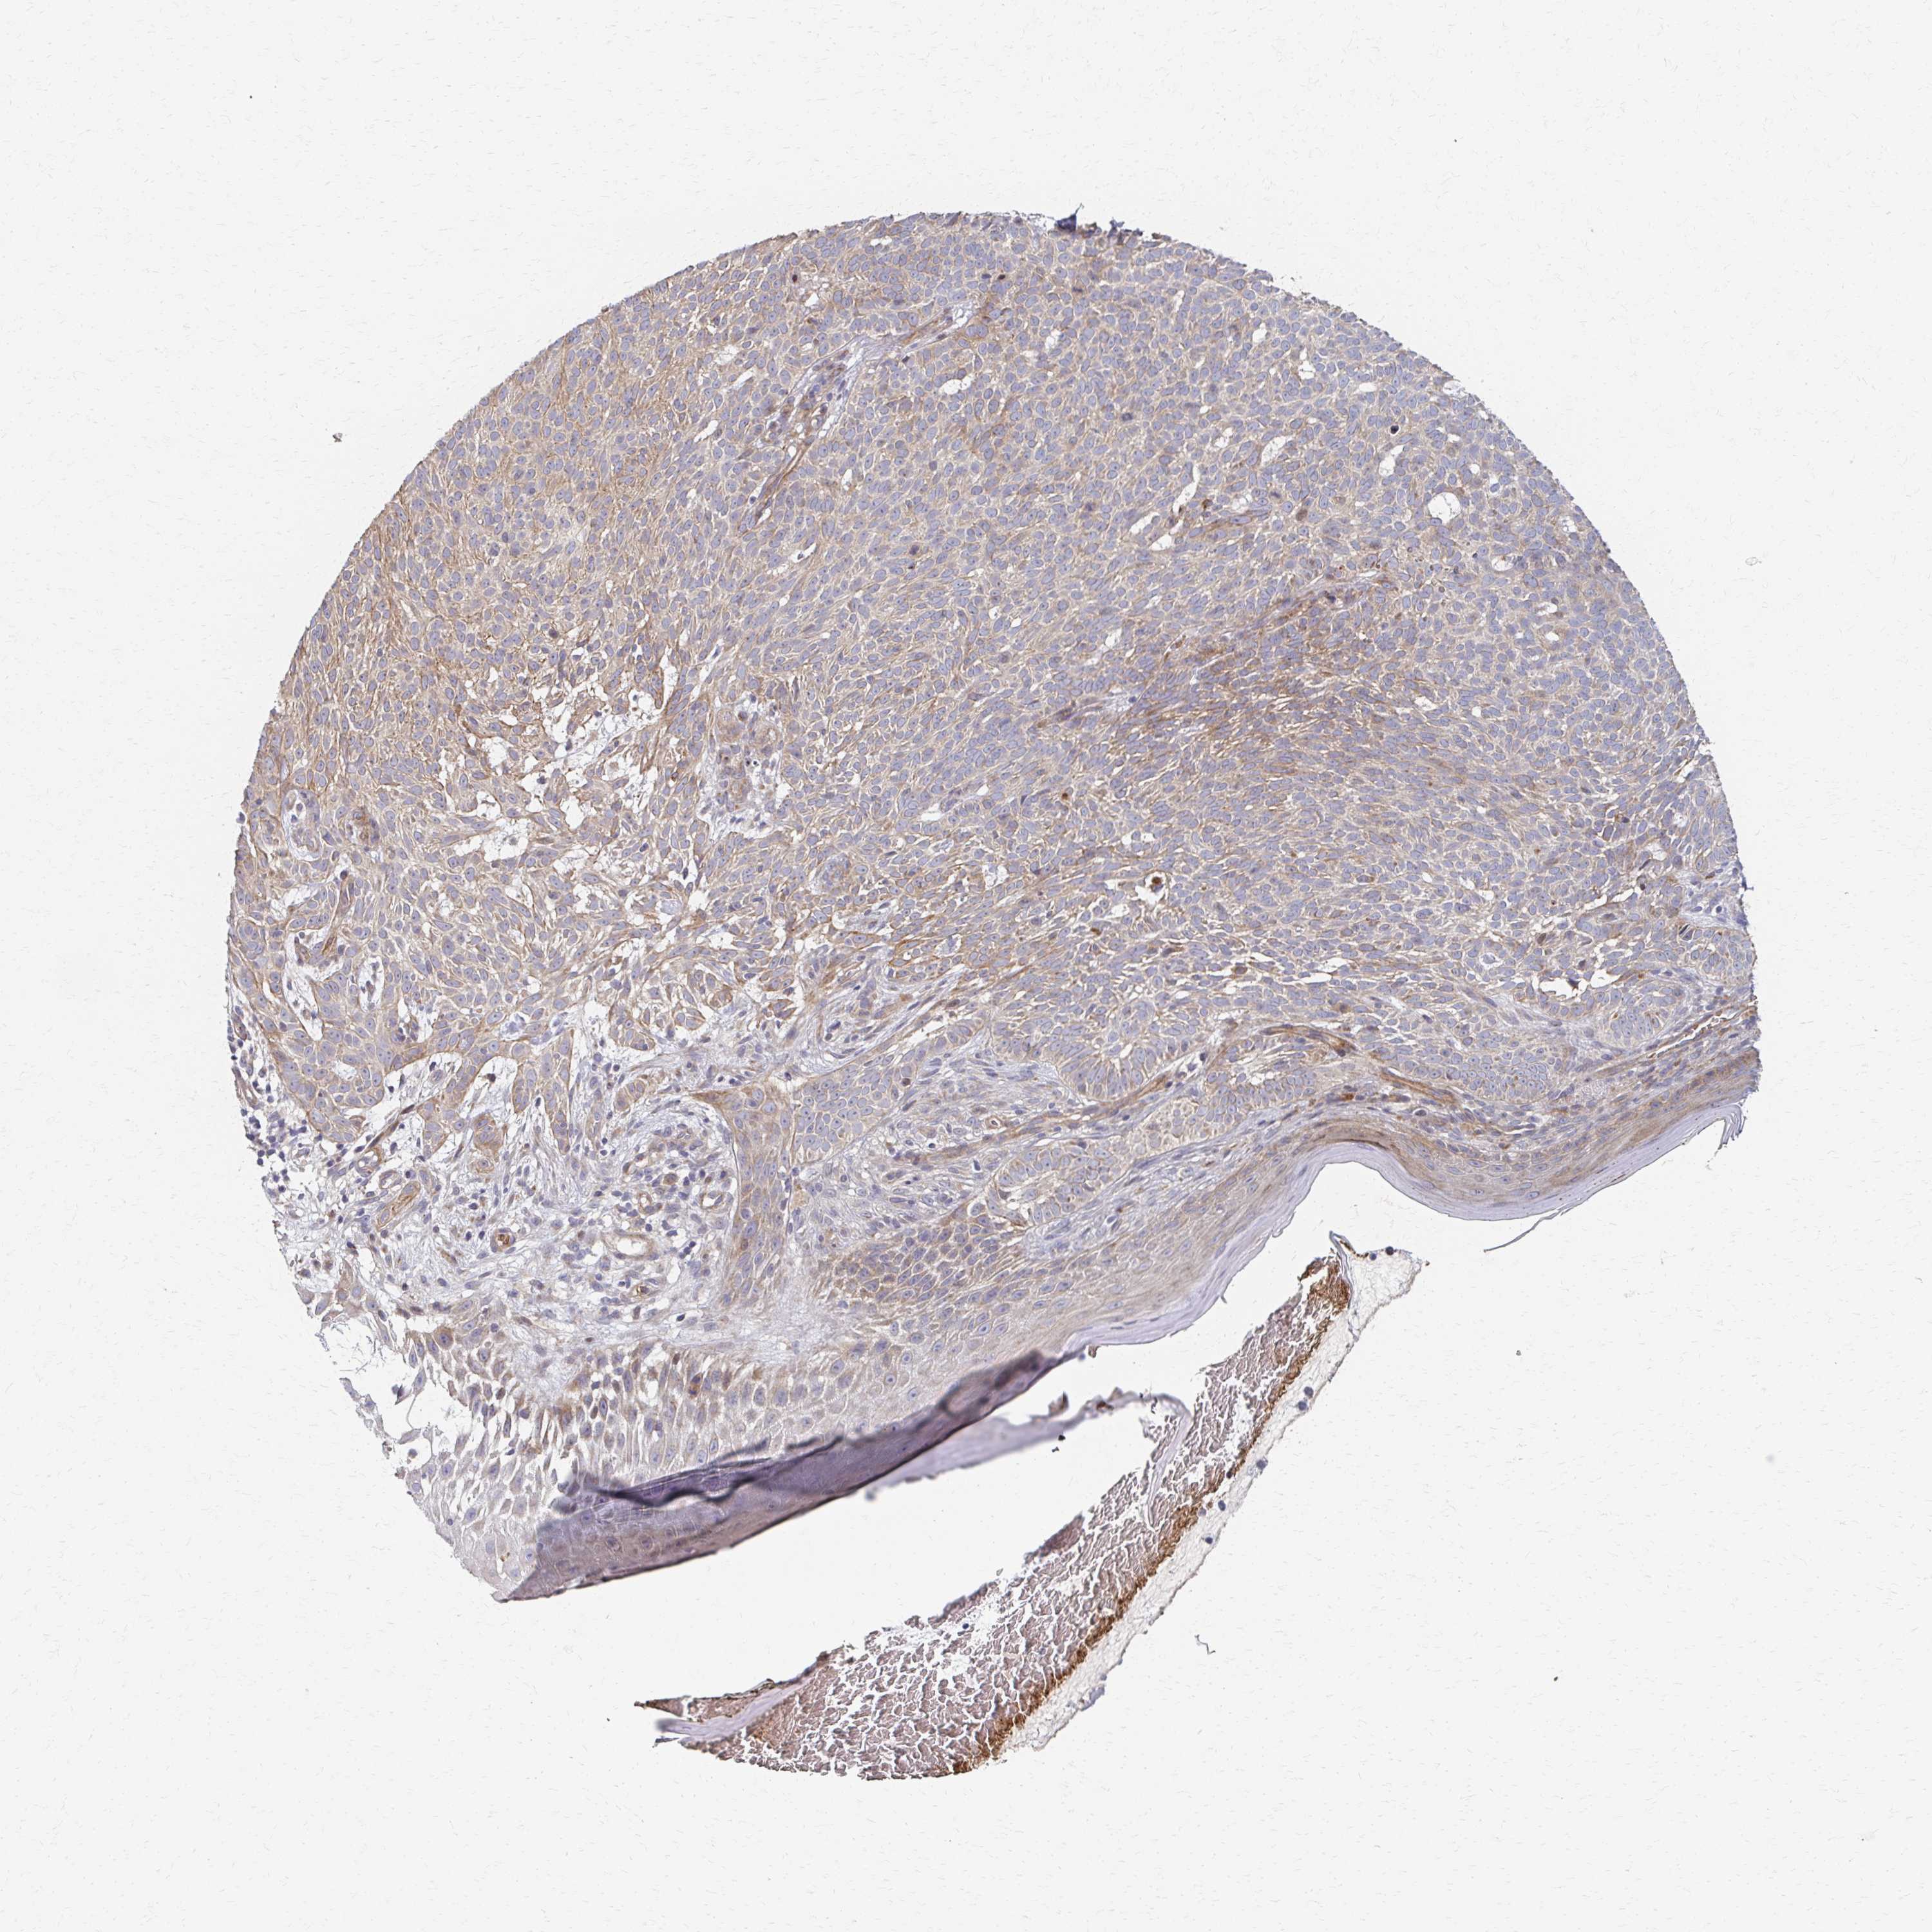

SKIN CANCER - Protein expressioni

A mouse-over function shows sample information and annotation data. Click on an image to view it in a full screen mode. Samples can be filtered based on level of antibody staining by selecting one or several of the following categories: high, medium, low and not detected. The assay and annotation is described here.

Each image is clickable and will lead to virtual microscopy that enables deeper exploration of all samples and also displays staining intensity scores, fraction scores and subcellular localization as well as patient and tissue information for each sample.

Antibody HPA059235

Staining

High

Medium

Low

Not detected

Intensity

Strong

Moderate

Weak

Negative

Quantity

>75%

75%-25%

<25%

None

Location

Nuclear

Cytoplasmic/membranous

Cytoplasmic/membranous,nuclear

Basal cell carcinoma

BCC, high aggressive